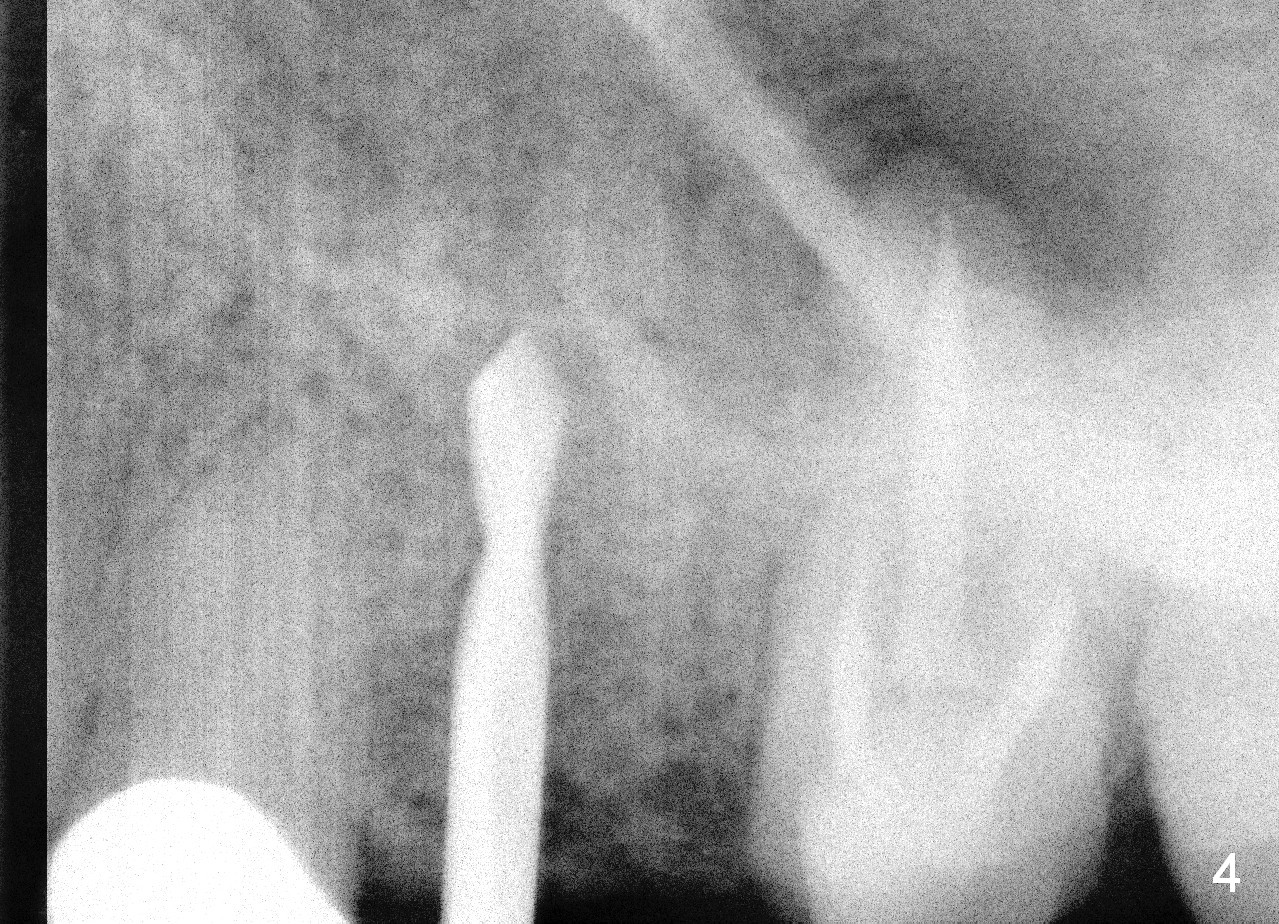

A 45-year-old lady is nervous about dental treatment. The missing tooth #13 was replaced by a 3-unit bridge. The latter is sectioned because the posterior abutment has caries. PA in Fig.1 is taken when root canal therapy and build up are finished. Fig.2 shows the wide edentulous area with a single-unit crown being tried in for #14. Osteotomy is initiated with the crown in place without cementation, since it is easy to determine the mesiodistal position (Fig.3 red lines). Without the crown in place, osteotomy tends to be distal. In this case, the osteotomy is later attempted to be moved distally with Lindamann bur and deepened to 14 mm from the gingival margin (Fig.4). A 2.5 mm reamer is being used at 50 RPM to increase osteotomy with difficulty. Drills have to used at high RPM instead (Fig.5 4x14 mm). A 4.5x14 mm tissue-level implant is placed with insertion torque >60 Ncm (Fig.6 I); a 4x3 mm abutment (A) is placed immediately for an immediate provisional. Fig.7 is taken 7 days postop to show the gingival recipient site formed by the provisional. The patient is so afraid of X-ray that the next one is taken 1.5 years post cementation (Fig.8). It appears that dense bone bundle forms between the crest and the 1st implant thread (adaptation functional change, arrowheads). The bone density continues to increase 2 years 8 months post cementation (Fig.9 *, 10); the bone has grown into the area between the 1st 2 threads (arrow).